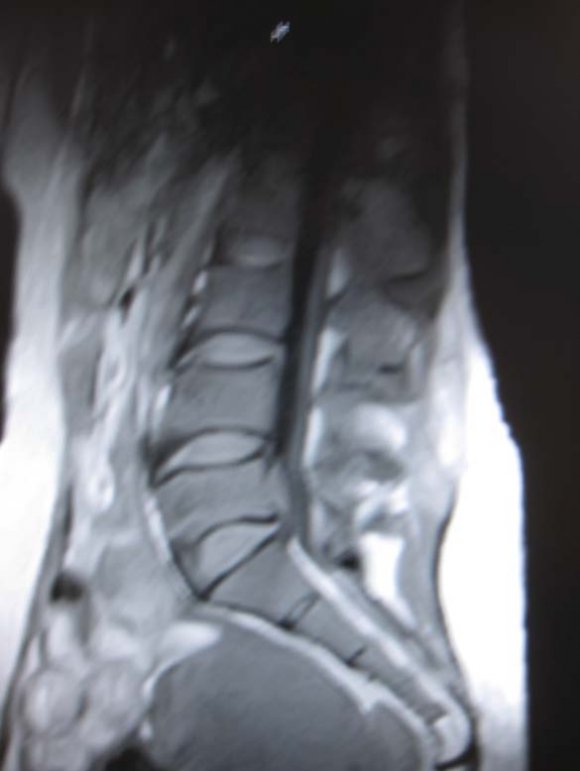

(b) there was no contraindications to MR imaging (e.g. pacemaker, aneurysmal clips, foreign body in globe etc). b) MRI Protocol MR imaging was performed at our hospital, using 0.3 Tesla Hitachi AIRIS 11 MRI machine, and spine phased-array coil. Technical factors used were T1W, T2W, STIR. Sagital acquisitions were used in screening while axial and coronal were used to evaluate the neural foramina. This was followed by T2 STIR images acquired in oblique coronal and sagital planes .Enhanced T1W images with Gadolinium pentate dimeglumine were used in cases of intra-spinal mass lesion or to evaluate herniated disc lesions where T2W images were degraded.

Technical specifications included a slice thickness of 3 and 4 mm for sagittal and axial sequences, respectively; a field of view of 26 and 20 cm for the sagittal and axial images, respectively; and a matrix of 192 by 256. The T 1 -and T 2 weighted axial sequences were stacked slices extending from the inferior aspect of L3 through the inferior aspect of S1.

This pioneer prospective MRI study is paramount because of paucity of such documentations in central African region. Our centre is the second MRI centre in Central African region and the earlier machine in another centre had broken down without any documentations of MRI findings related to LBP. MRI defines the lumbo-sacral spine diagnosis with high specificity allowing the most approximate therapeutic decisions [9]. Back pain is the most frequent cause of limitation of activity among individuals who are less than forty-five years old. [4]. Our largest studied population with low back pain, 31.25% was in the 50-59 age range with male to female ratio of 1:1.14. This is followed by 29% in the 40-49 age range with male to female ratio of 1:0.4. This agreed with high incidence of low back pain in the work force with attendant negative impact on productivity and economy [1].Annually, back symptoms occur in 50% of working age adults in USA [1]. Each year, there are approximately 500,000 Workers' Compensation and personal-injury cases dealing with low-back pain [4]. In this study, detected number of pathologies outweigh the number of studied population. This is because multiple pathologies can exist in one patient . The high signal intensity of the cerebrospinal fluid and epidural fat in T2W sequence makes T2W sequence the most useful in evaluation of discal lesion, which is dorminant pathology as in our study [9]. The commonest pathology in this study is disc hernia with 16 cases (33.3%) with male to female ratio of 3:1. 10 cases (62.5%) of herniated disc occurred at L4/L5 disc level followed by 4 cases (25%) at L5/S1 disc level. At L4/L5 level male to female ratio is 4:1 while equal male to female ratio is seen at L5/S1 level. This predominance of disc herniation at L4/L5 and L5/S1 levels is supported by previous study [12] The reducing gender difference is accounted for by the increasing degeneration, laxity, demineralisation and dessication with ageing in both sexes [9]. This is corroborated by the articular facet degenerative changes seen in almost all cases of disc herniations shown as height reduction and subluxation of the ligamentum flavum of the facet joints [9,12].

9. Global Journal of Medical Research

Disc herniation can be used to describe a wide spectrum of abnormalities involving disk extension beyond the interspace, from a bulge to a frank extrusion and sequestration; [11]. The terms used to classify disks were defined as follows: normal, no disk extension beyond the interspace; bulge, circumferential symmetric extension of the disk beyond the interspace (around the end plates); protrusion, focal or asymmetric extension of the disk beyond the interspace, with the base against the disk of origin broader than any other dimension of the protrusion; and extrusion, more extreme extension of the disk beyond the interspace, with the base against the disk of origin narrower than the diameter of the extruding material itself or with no connection between the material and the disk of origin [9,11].Sequestered disc are free disc fragment which may migrate below or above the interspace [6]. On MRI examination of the lumbar spine, many people without LBP have disk bulges or protrusions but not extrusions, thus discovery by MRI of bulges or protrusions in people with LBP may frequently be coincidental [11]. There is a hypothesis that the prevalence of extrusions in people with symptoms of LBP may be substantially higher than in people without symptoms [11]. Sequestered or free fragment has high T2 * W signal because their increased water content produces an increase in signal intensity [6]. When it is behind the parent disc, it is round in configuration but oblong on further separation [6]. Annular defects or fissure which can be demonstrated by MRI as decreased signal on the T 2 -weighted image may be a fore-runner to disc hernia and are frequently asymptomatic [11] But any pain , possibly results from leakage of the contents of the nucleus pulposus into the epidural space, with related nerve irritation [11]. The reported prevalence of posterior radial tears at autopsy in asymptomatic people is 40 percent for those between In our study, no distinction was made between disc protusion and extrusion, rather cases where there is protusion of disc anteriorly and behind anterior longitudinal ligament was considered separately and termed disc anteropulsion. 6 cases (12.5%) anteropulsions were seen. Using MRI in 67 people without symptoms, Boden et al. found herniated disks in 20 percent of the people less than 60 years old and in 36 percent of those 60 years of age or older [11]. But our study included symptomatology criterion and discovered 60% of patients 60years and above had disc hernia. Low back ache is one of the most common causes of morbidity in elderly patients and could be due to multiple aetiologies like degenerative-inflammatory lumbar spinal pathology . [2,13] Multiple levels of disc hernia was seen in 56.25% of our patients. MRI examination of 41 women without symptoms showed that 54 percent had a disk bulge or herniation at one or more disk spaces, although only L3-4, L4-5, and L5-1 levels were examined [11]. b) MRI is the preferred investigation for confirming lumbar disc herniation, nerve root entrapment, radiculopathy, and spinal canal stenosis [3]. Lumbar spine stenosis (LSS) is subdivided into relative and absolute LSS according to the anteriorposterior diameter of the spinal canal (physiological value is 22-25 mm) [7]. Relative LSS is when spinal canal measures 10-12 mm in diameter and usually asymptomatic. Whereas absolute LSS (spinal canal <10 mm in diameter) is often symptomatic and is associated with absence of free subarachnoid space [7]. The lateral recess can also be considered in LSS definition (physiological diameter is 3-5 mm) and stenosis is considered if it has a diameter of <2 mm [7]. 32(66.66%) of our studied population had lumbar stenosis. LSS can be mono-segmental or multisegmental, and unilateral or bilateral. Pathoanatomically, stenosis can be classified as central, lateral or foraminal. This is often the sequllae of degenerative disc hernia [7]. Herniated disc is classified into central, centro-lateral and lateral, the commonest is centro-lateral. [6]. Laterally herniated discs and smaller focal disc herniations may be difficult to diagnose with only sagital imaging. Axial imaging will help and has become a routine examination protocol to assess the degree of lateral, neural canal, nerve root and cord involvement [12]. Depending on the extent of the degeneration, central, lateral and foraminal stenosis can occur alone or in combination. The L4-5 spinal discs are most frequently affected by LSS, followed by L3-4, L5-S1, and L1-2 [7].This highest occurrence of lumbar stenosis at L4/L5 is noted in our study with disc hernia the ages of 50 and 60 years and 75 percent for those between 60 and 70 [11]. availability of advanced imaging techniques. [7].